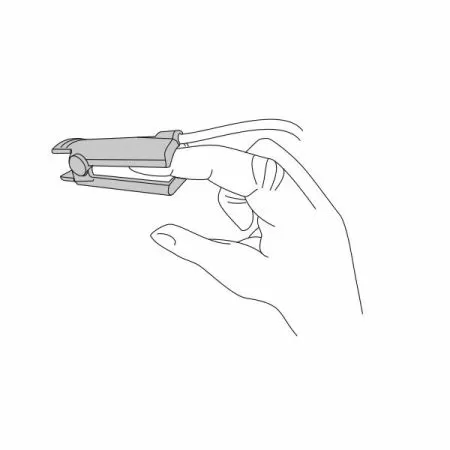

Датчик детский (манжета) |

1 |